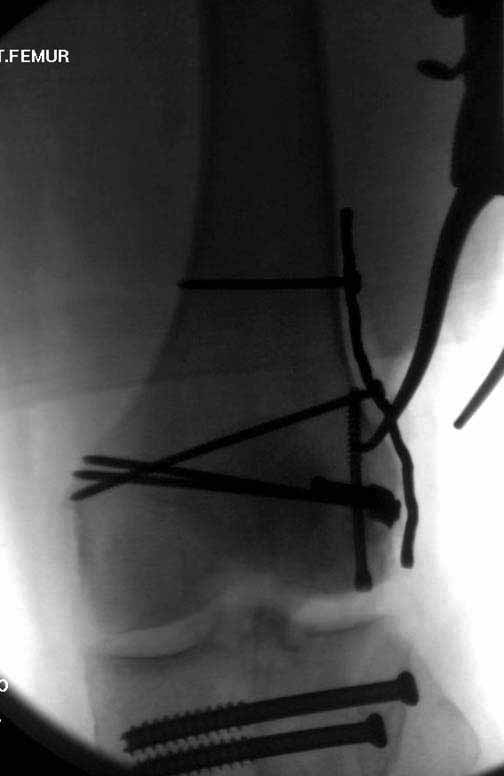

У больных как в этом случае, с вовлечением двух мыщелков правильно, что сделали вытяжение до операции. Здесь имеется флексионный компонент на другой стороне, и я бы рекомендовал операцию делать из двух доступов. Сперва фиксировать медиальную колонну custom made пластиной, обычно 1/3 тубулярной пластиной в 4.5 мм, потому что пока производители опаздывают с медиальной пластиной.

Пластину надо устанавливать на апексе перелома, иначе фрагмент начнет сползать. А на второй стороне, если имеется большой одиночный фрагмент тогда проблем не бывает, и их можно собрать компрессирующими винтами. Проблема наступает тогда когда многофрагментраность на латеральной стороне, где надо применить комбинированный метод, иногда несколькими пластинами. Или сменой позиции установки пластины, чтобы максимально прикрыть перелом и создать боковую поддержку.

Здесь пример медиальной пластины и латеральный комбинированный метод (у второго больного старый перелом тибиал плато, леченный где то и когда то)